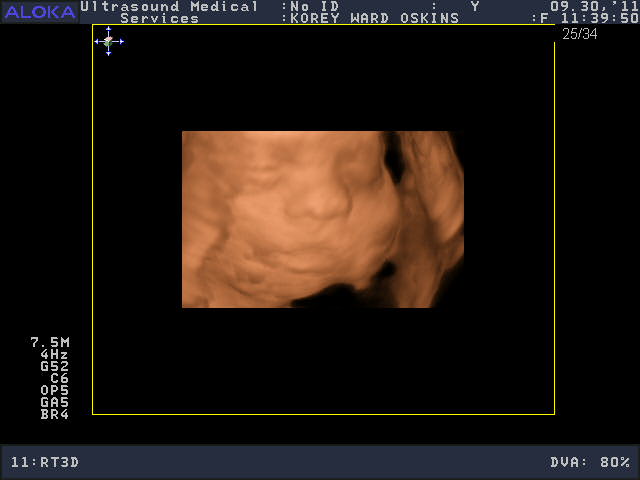

He was a very stubborn baby, so it was really kind of nerve-wracking at first thinking we might not get a single good picture. His face was squished up against the placenta and he wouldn’t budge. You’ll see that in the pictures below; it looks like an enveloping cloud or a scallop shell. Finally he moved a bit and we got some glimpses of his face. We saw him make some facial expressions, wiggle his fingers, and move his mouth around. We were curious to see whose nose he would have, and in some pictures, it looks like he has Josh’s, in others, mine.

So who do you think he looks like?

He is sooooo cute! Personally, I think he looks like ME.